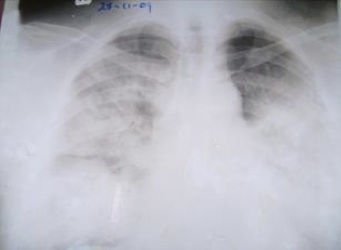

Il s’agissait d’un homme âgé de 45 ans d’origine Malgache, médecin, domicilié à Itaosy Antananarivo, sans antécédent particulier admis au service de Réanimation médicale de l’Hôpital Joseph Raseta Befelatanana (CHU d’Antananarivo) le 28 Novembre 2009 pour une dyspnée aiguë.Le début de la maladie remonterait au 27 novembre 2009 par un syndrome grippal traité sans succès avec du paracétamol et des mucolytiques (N acétyl cystéine).Le patient a été hospitalisé en réanimation devant la majoration de la dyspnée avec orthopnée.A l’admission en réanimation, le patient était conscient, l’hémodynamique était stable. On notait une polypnée à 44 cycles/min, une cyanose, des sueurs, des râles crépitant diffus dans les deux champs pulmonaires et une hyperthermie à 40°C. Devant ce tableau clinique, la radiographie pulmonaire (Fig. 1) a montré des opacités alvéolaires diffuses, bilatérales évocatrices d’un œdème aigu du poumon. L’électrocardiographie (ECG) montrait une tachycardie sinusale régulière.